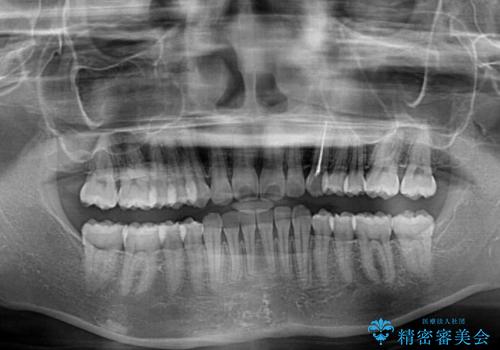

- 前歯のデコボコと奥歯の不正咬合を気にして来院された患者様です。

左右の大臼歯が全て鋏状咬合(シザーズバイト)になっており、治療が難航することが予想されましたが、インビザラインにより治療を行うこととしました。

最難関と思われたシザーズバイトは比較的短期間で解消されました。

しかし、治療中に2度の出産を経験され、治療期間は長くなってしまいましたが、咬みやすく、清掃しやすい歯列を獲得することができました。